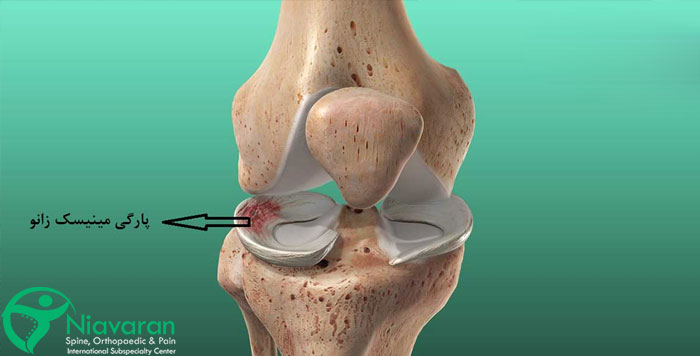

پارگی مینیسک زانو چیست

پارگی مینیسک زانو یکی از شایعترین بیماری های زانو است که معمولاً به دلیل پیچ خوردن ناگهانی زانو، چرخش شدید یا فشار زیاد روی مفصل رخ میدهد. این آسیب بیشتر در ورزشهایی مانند فوتبال، بسکتبال و اسکی دیده میشود. همچنین افزایش سن و تحلیل رفتن غضروفها، احتمال پارگی مینیسک را افزایش میدهد. جالب است بدانید افرادی که حرکات ناگهانی و پرفشار انجام میدهند یا دچار ضعف عضلانی در اطراف زانو هستند، بیشتر در معرض این آسیب قرار دارند. پارگی مینیسک ممکن است بهصورت جزئی یا کامل رخ دهد که هرکدام علائم و روشهای درمانی متفاوتی دارند.

انواع پارگی مینیسک زانو

پارگی مینیسک پا ممکن است به شکلهای مختلفی اتفاق بیفتد. پزشکان متخصص، صدمات وارده به این بخش از زانو را در 6 نوع مختلف معرفی میکنند که در ادامه، هر کدام را توضیح میدهیم: